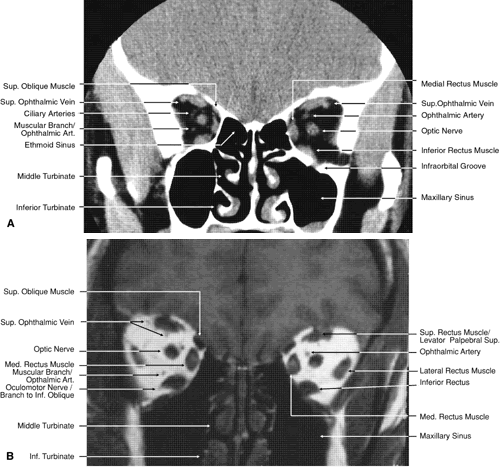

The globe is shown in Figure 12. The orbit and periorbital structures are shown in Figures 13 through 16, and the optic canal is shown in Figures 17 through 26. The cavernous sinus and optic chiasm are shown in Figures 27 and 28, and the posterior visual pathway and cranial nerves are shown in Figures 29 through 33.

Fig. 20. Coronal images through orbital apex. A. Computed tomography scan. B. T1-weighted magnetic resonance imaging. C. Anatomic section of a cadaver head at the level of the orbital apex.

Fig. 21. Coronal images through optic canal. A. Computed tomography scan. B. T1-weighted magnetic resonance imaging.

Fig. 22. Axial images at the level of inferior orbit. A. Computed tomography scan. B. T1-weighted magnetic resonance imaging.

Fig. 23. Axial images at the level of midorbit. A. Computed tomography scan. B. T1-weighted magnetic resonance imaging.